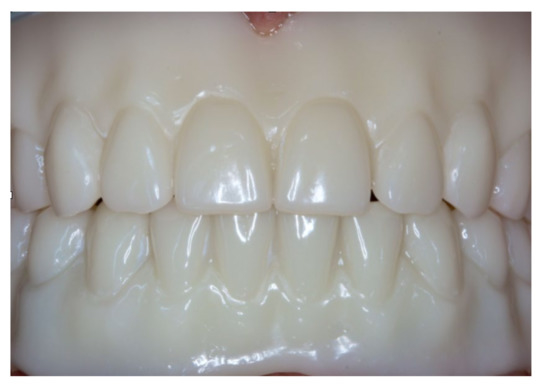

Figure 16.

Polished implant-supported overdenture in the lower jaw ready for insertion.

Figure 17.

Basal view of the implant-supported overdenture in the lower jaw and its supporting framework equipped with intermediate retention inserts.

Figure 18.

Polished complete denture in the upper jaw ready for insertion.